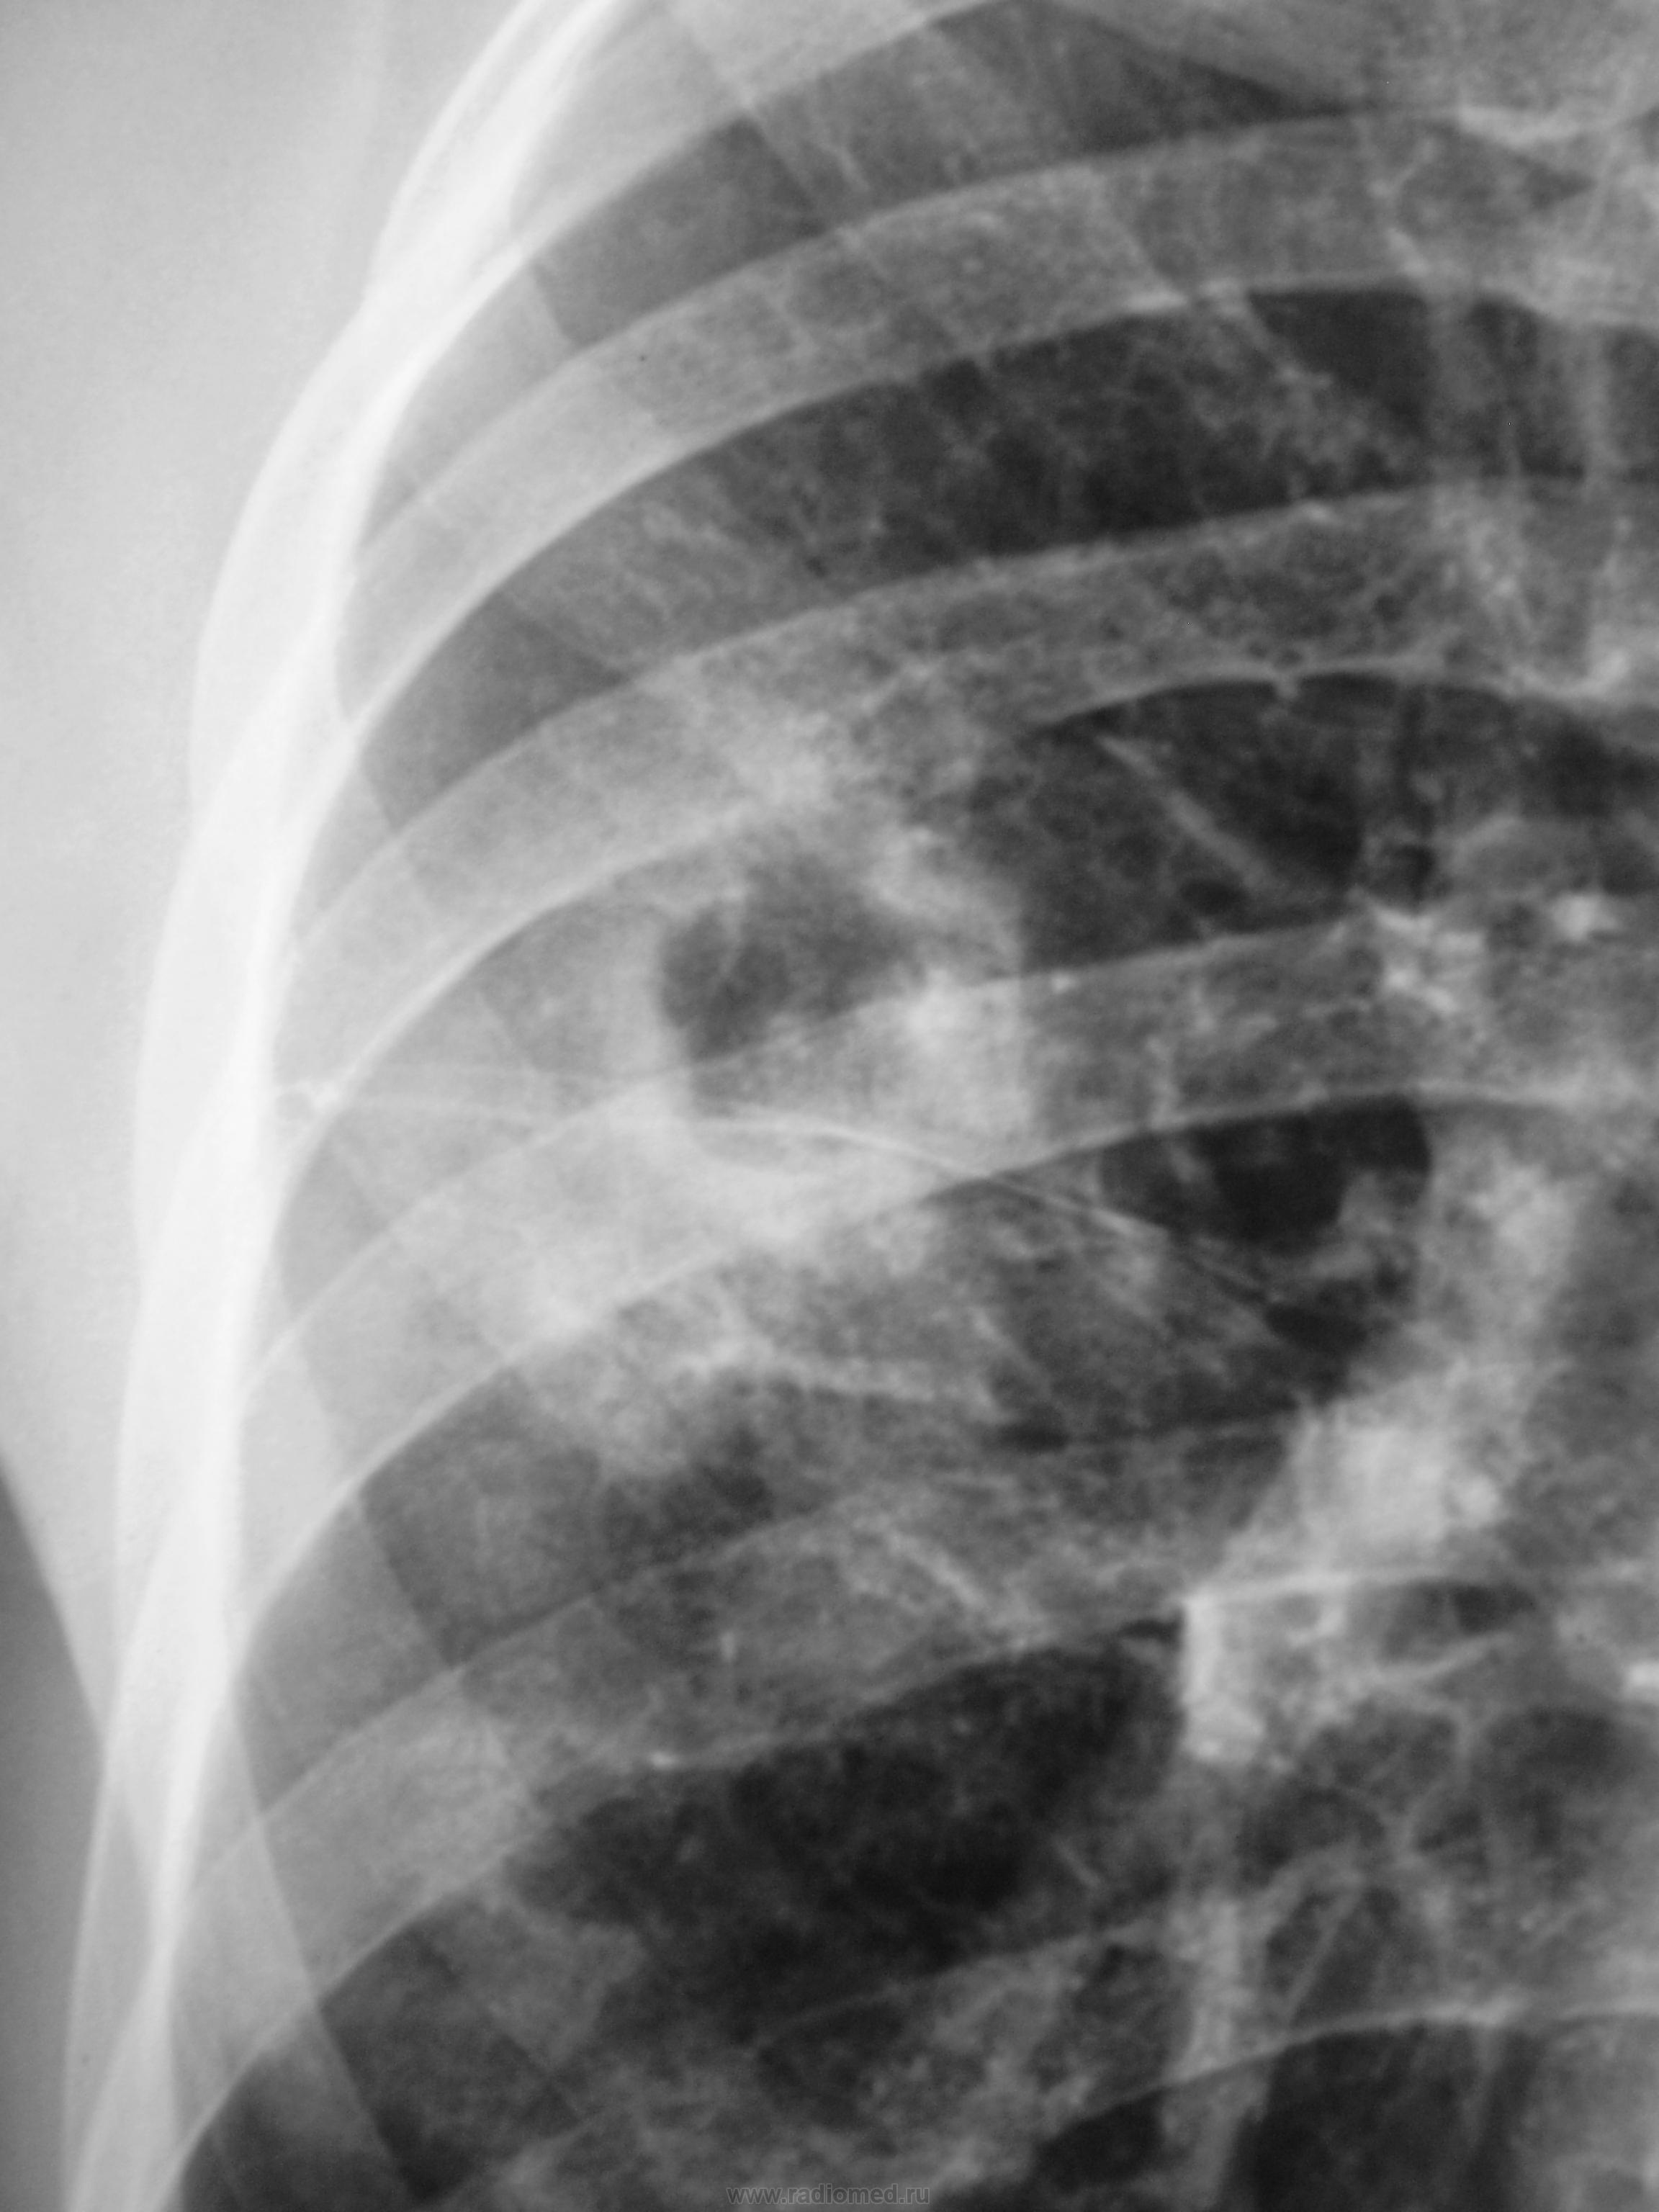

Прошло 3 месяца, и сегодня, фтизиатр прислал на «контроль», взятого на заметку.

Стало ясно, что линейная томография в данном случае не повредит.

Какое мнение будет после томографии у уважаемых коллег?

Формально фтизиатры поставят диагноз инфильтративный туберкулез S6 правого легкого, фаза распада. Но, я не зря спросил про возраст больного. У молодых людей нижнедолевой туберкулез особенно в 6 сегменте часто связан с поражением внутригрудных лимфатических узлов. Пути распространения инфекции лимфобронхогенное. Подтверждением этого является обнаружение при бронхоскопии различных форм активного туберкулеза (инфильтративный, язвенный и лимфобронхиальный свищ). При бронхоскопии у больного могут найдут специфическое поржение бронхов. Лимфогенный путь распространения напоминает раковый лимфангиит . О лимфогенном распространении инфекции указывает прединфильтратная сетка, которую хорошо видно на рентгенограммах. О поражении лимфатических бронхопульмональных узлов свидетельствует вовлечение в процесс плевральных листков в виде воспалительного уплотнения междолевой плевры, а также наклонность к раннему образованию распада. Известно,что у взрослых трудно выявить изменения со стороны ВГЛУ, так как они не часто достигают той величины, как у детей. Умеренно выраженное увеличение бронхопульмональных л/у на КТ диагностируется только при контрастировании. Таким образом, предварительный патогенетический диагноз звучал бы так : туберкулез внутригрудных лимфатических узлов бронхопульмональной группы справа, осложненный бронхолегочным поражением в S6 с распадом. Необходимо построить патогенетический диагноз, так как специфические изменения в лимфатических узлах требуют более длительного лечения. Такова моя точка зрения на диагноз у представленного пациента. С уважением Ваш NIkolas